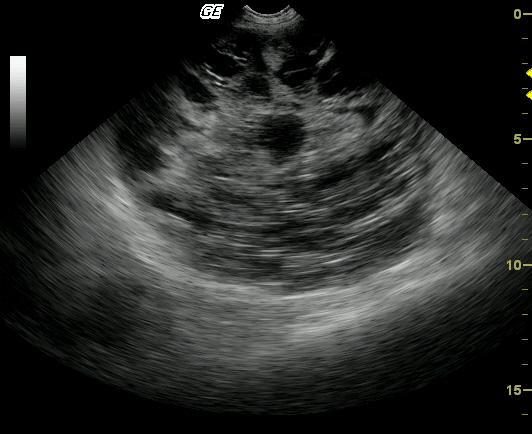

Large cavitated mass with bordering inflammation and suspect omental and mesenteric adhesions. Neoplasia, either benign or malignant arising from a regional soft tissue structure, mesentery or omentum is primarily suspected. Also considered are inflammatory, infectious (parasitic?), granulomatous, hematoma.

A large, well-encapsulated, cavitated and septated mass is present within the peritoneal cavity. The mass is bordered by echogenic omentum and mesentery, which may be adhered. The origin of the mass is not apparent on these images.

The origin of the mass could not be discerned by the sonogram even though it enveloped intestine and mesentery. The patient is clinically normal at a 5-month follow-up. A repeat sonogram was suggested but had not been performed. After surgical resection, no adjunctive therapy was administered.